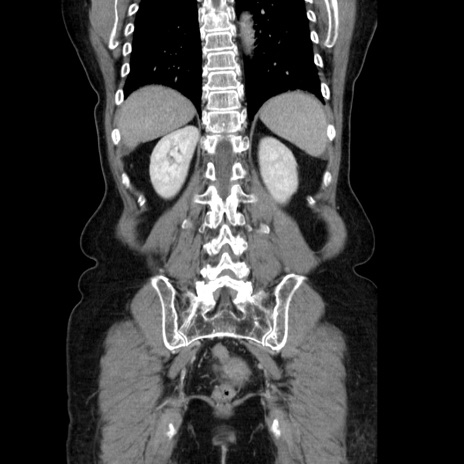

症例5(冠状断像)

【症例】70歳代女性

【主訴】お腹が張る

【現病歴】1週間くらい前から腹部膨満の自覚あり。昨日夜から増悪したため、本日救急外来受診。

【身体所見】意識清明、BT 36.5℃、BP 165/106mmHg、HR 80bpm、SpO2 98%、腹部:膨満、軟、自発痛・圧痛なし、触診にて不快感あり、腸蠕動音:減弱

【データ】WBC 12600、CRP 1.04